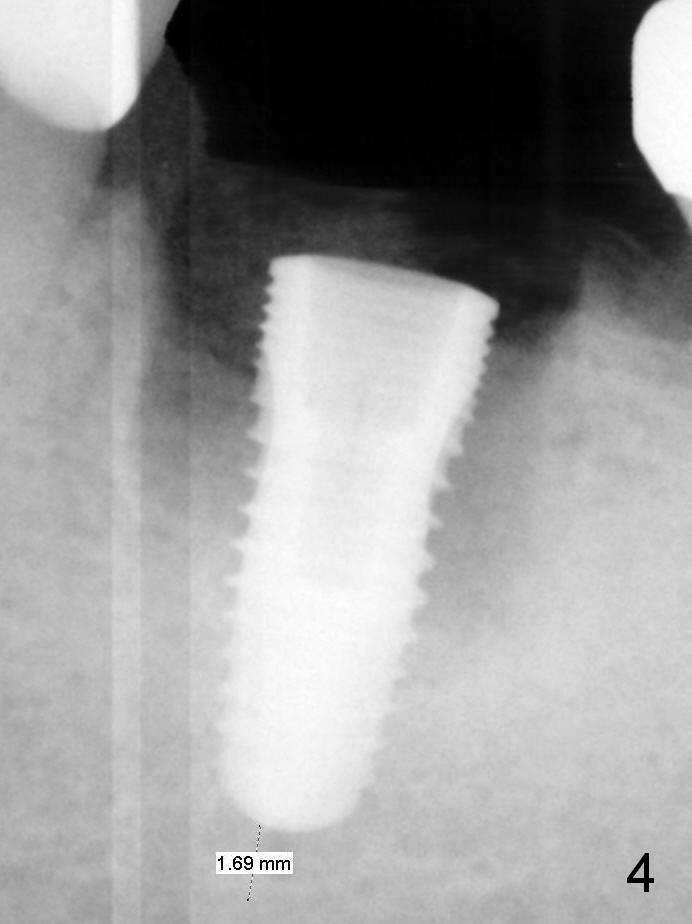

When a 5x12 mm bone-level implant is placed (Fig.4), there is a gap mesiobuccally, which is later filled with bone graft (Fig.5 *). A large abutment (7.8x4(3) mm) is placed immediately (Fig.5 A) for an immediate provisional (P) to close the sockets.